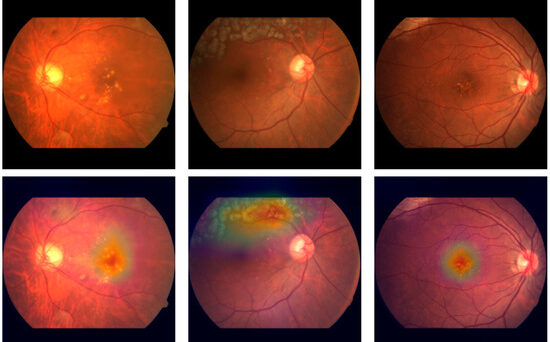

Implementing the AI Boutique within the Freedom Nano platform has already shown significant positive impacts in various clinical settings, notably enhancing diagnostic capabilities, clinical efficiency, and patient satisfaction. For instance, integration of AI analysis in ophthalmology for conditions such as diabetic retinopathy has proven highly effective in early disease detection and management.